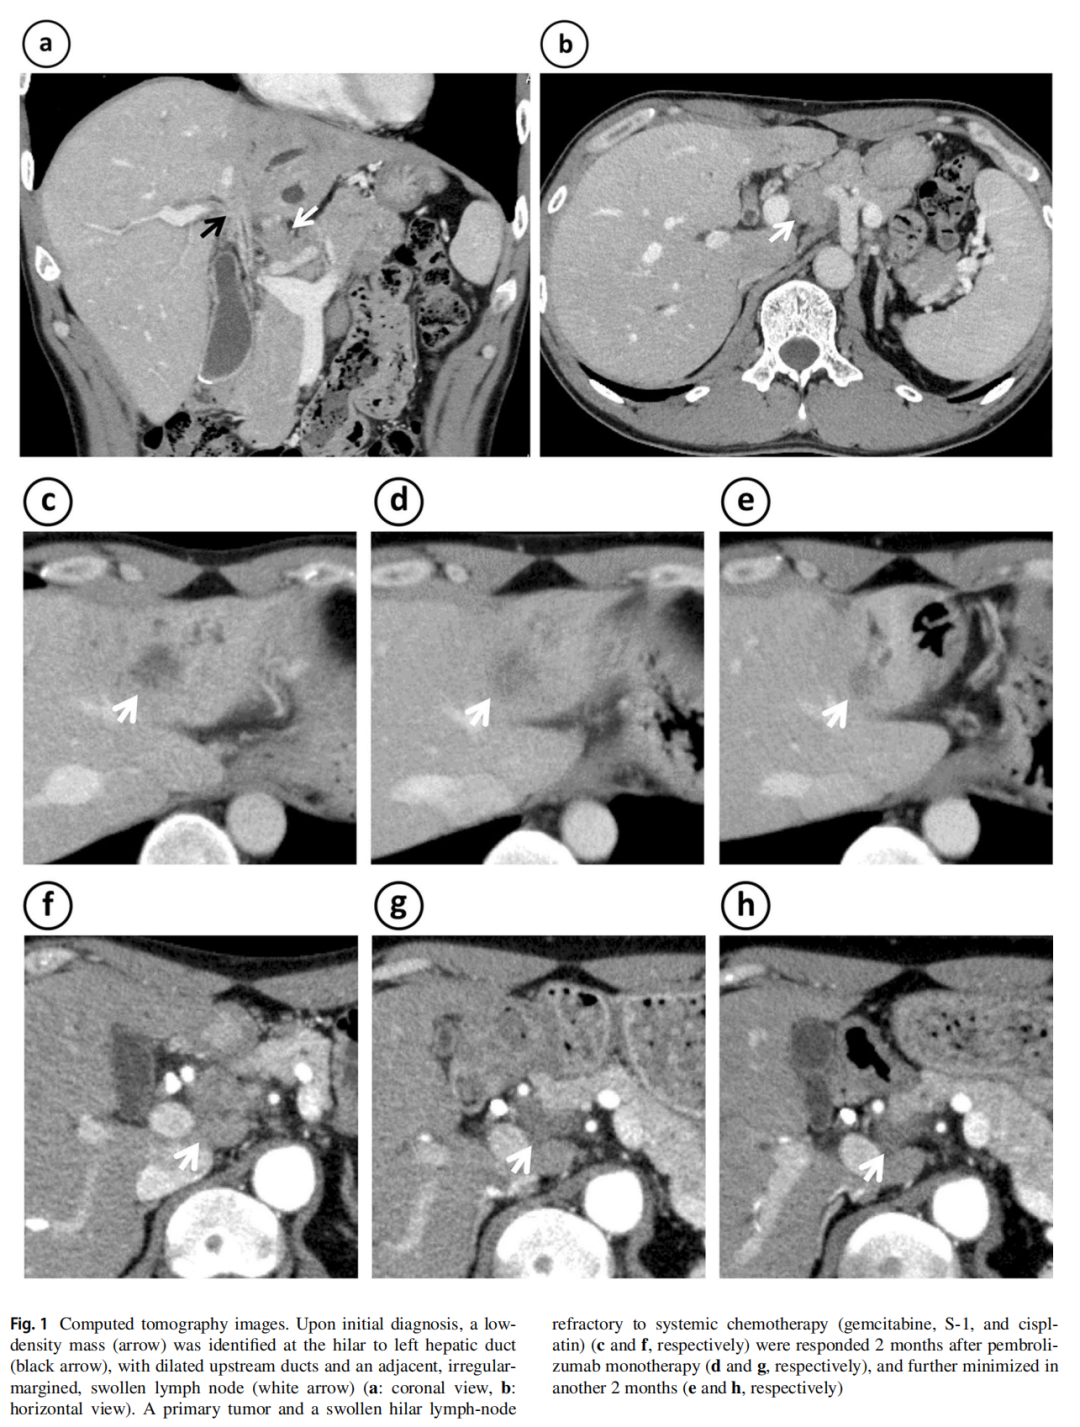

增强CT显示肝门胆管及脐部有直径25mm的肿块,肝门周围淋巴结不规则肿大(图1a,b)。鉴于淋巴结转移已扩散至肝总动脉和腹腔动脉周围,临床医生判断不可手术。超声内镜引导下的细针穿刺活检术样本EUS-FNAB图2a显示小的腺癌碎片散布在大量白细胞、红细胞和纤维组织内(图2b,c)。内镜下逆行胆管造影证实肝门胆管狭窄(图3a)。在胆管狭窄部位进行了四次钳夹活检(图3b),结果显示存在多簇腺癌组织(图3c,d)。钳夹活检样本的免疫组化(IHC)显示,错配修复(MMR)蛋白表达正常(MLH1,MSH2,MSH6和PMS2)。

图1 患者CT检查结果

患者接受吉西他滨、顺铂和S-1的全身化疗,缓解持续4个月,但在第7个月时淋巴结肿大复发(图1c,f)。经患者同意,进行了MSICDx和MGPT检测。由于FNAB或钳夹活检样本的组织量不足以进行两项检测,因此将FNAB样本分配进行MSI检测,将钳夹活检样本分配进行MGPT检测。MSI检测显示MSS(5个位点均未改变)(图2e)。然而MGPT结果显示了多个基因变异,包括MSI-H和高肿瘤突变负荷(TMB-H) (10.09Muts/Mb;TMB-H≥10Muts/Mb),提示免疫检查点抑制剂有效。患者随后开始接受帕博利珠单抗单药治疗(200mg / 3周),在开始治疗2个月后缓解(图1d,g),并在继续接受2个月治疗后出现进一步缓解(图1e,h)。患者及其家人接受了Lynch综合征可能性的遗传咨询。向患者介绍了Lynch综合征的概念和MMR基因的胚系检测的必要性,但患者拒绝接受检测。

标准化疗对晚期BTC的疗效有限,基于CDx和MGPT的精准医疗开启了新的治疗格局。在BTC的精准医疗中,MSI-H是最有前景的分子标志物,因为帕博利珠单抗显示出显著的缓解率(40.9%)和总生存期的延长(24.3个月)。本文BTC患者对标准化疗耐药,但对帕博利珠单抗表现出良好的应答(图1c-h)。个体化精准医疗需要高度的准确性和一致性,但本文病例的MSI检测和MMR IHC存在不一致的问题。